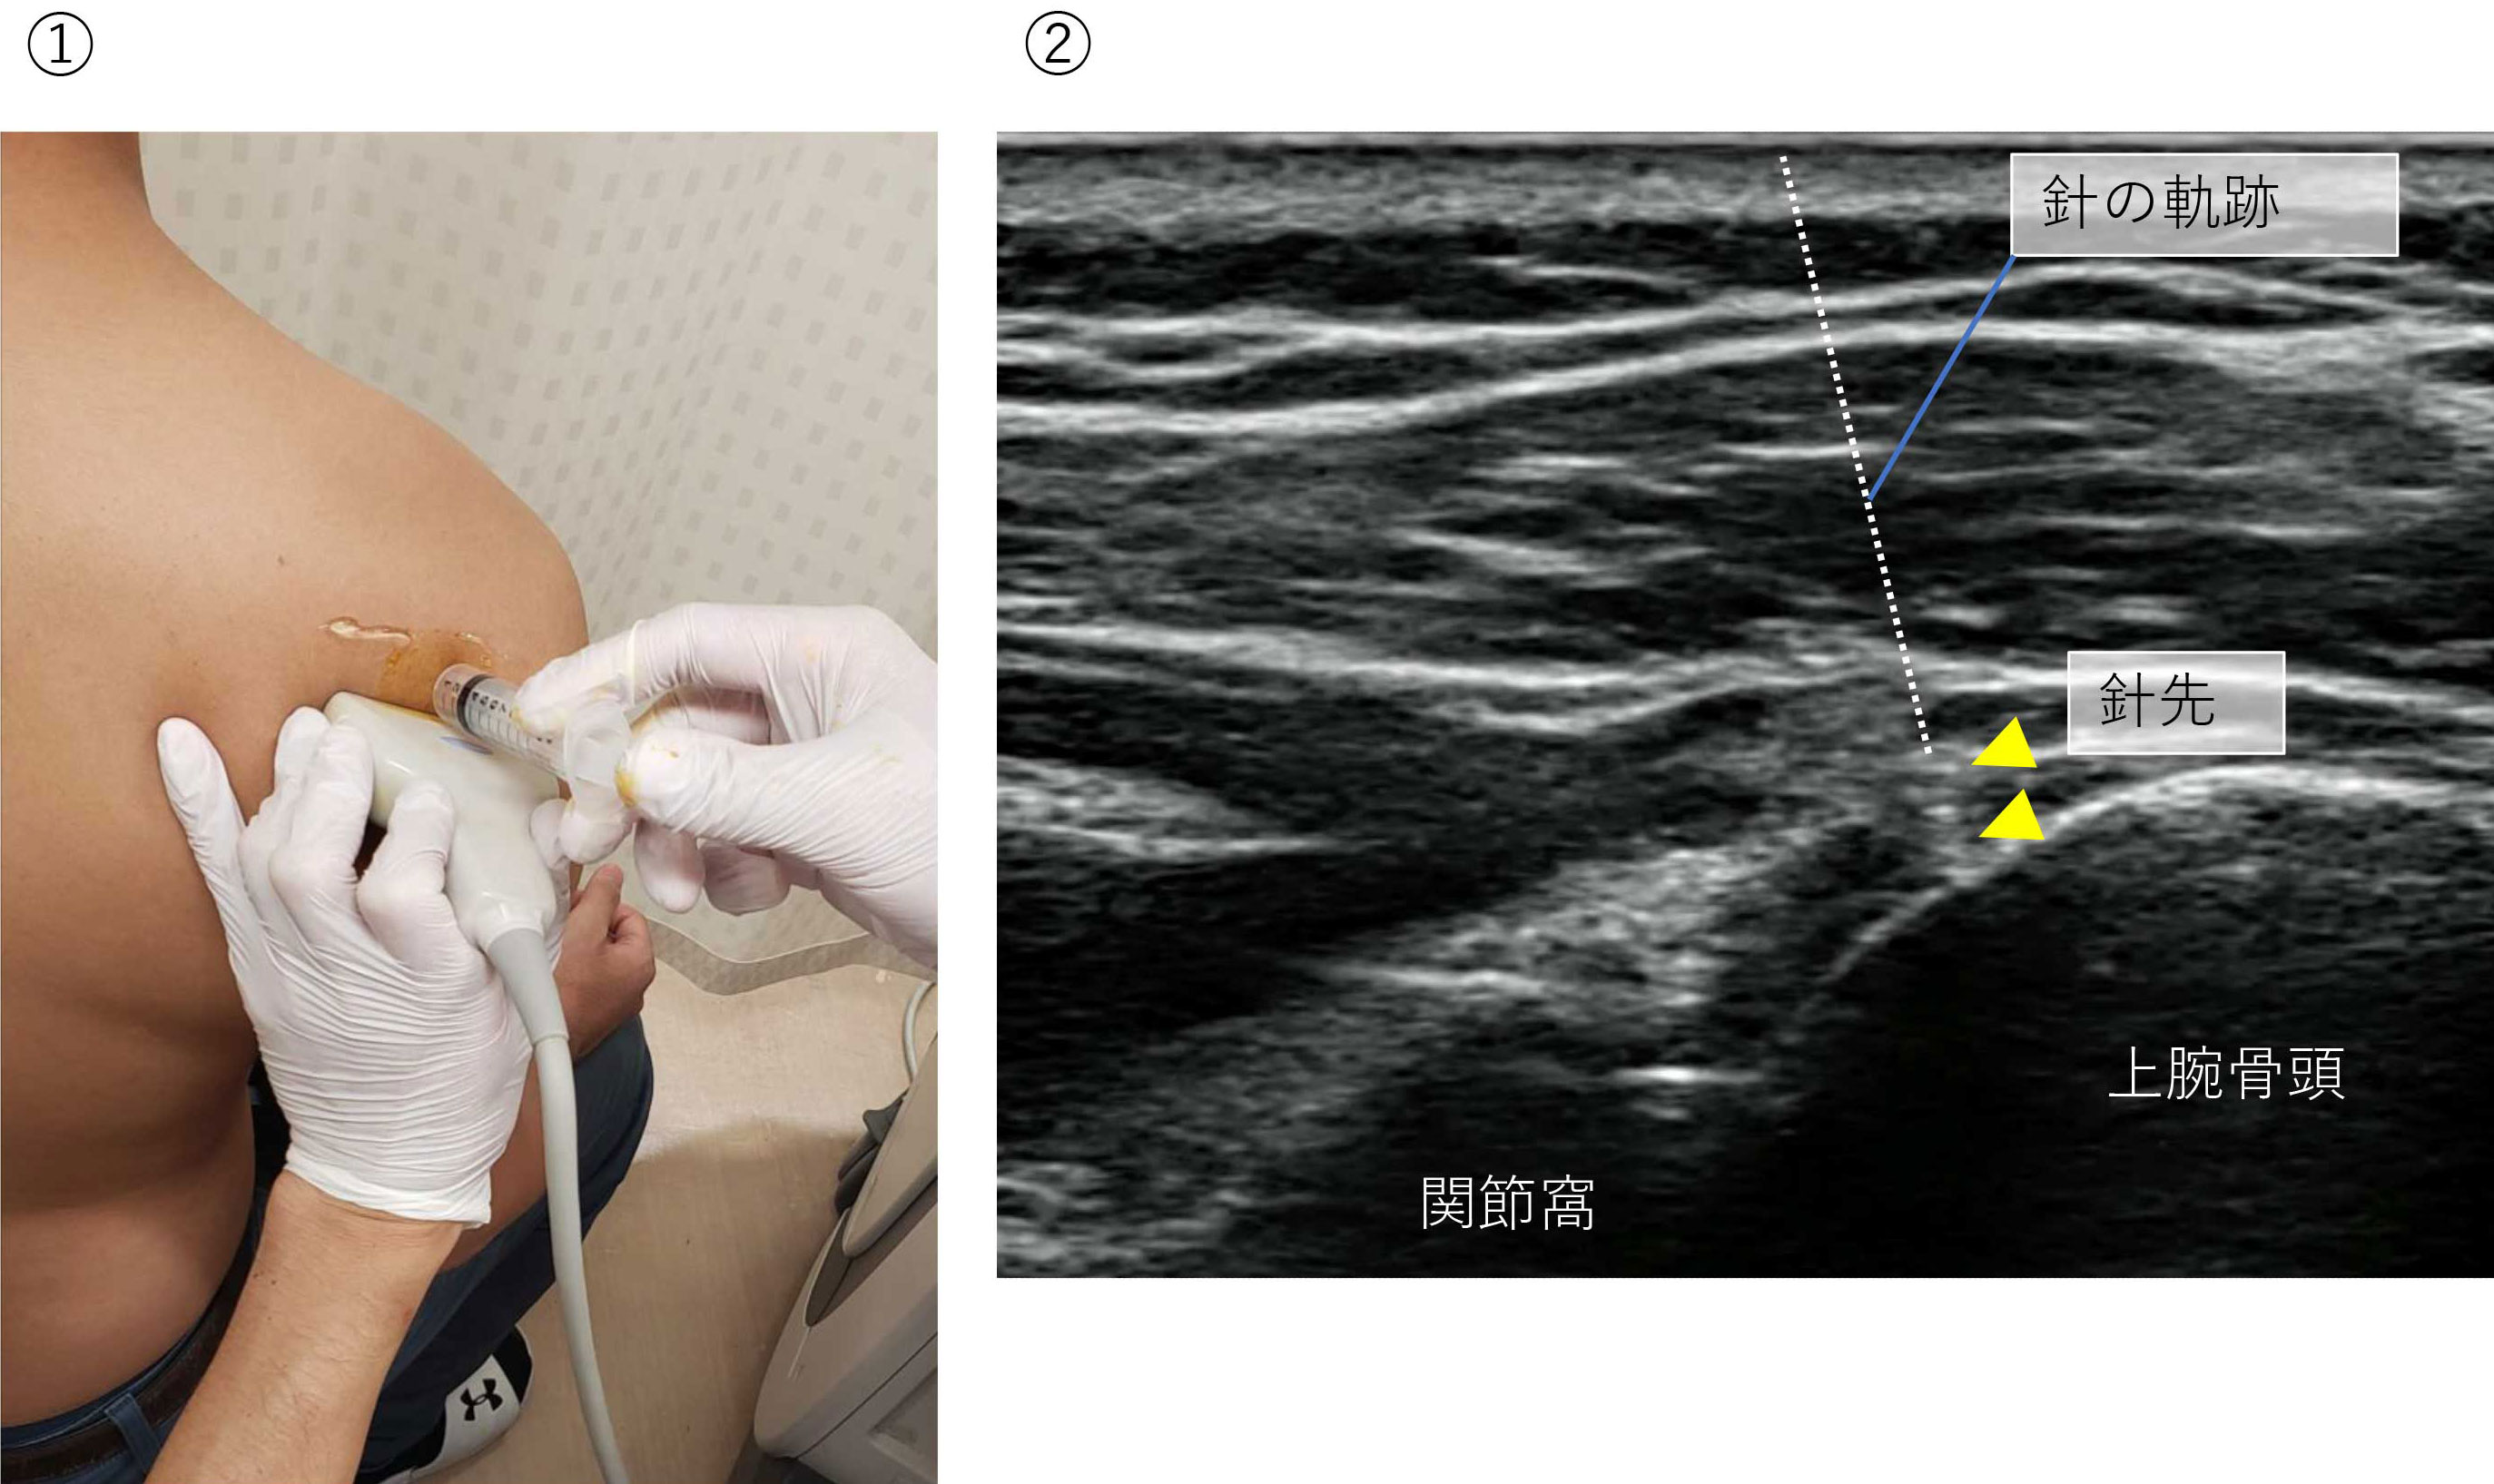

MRI(関節造影)

注射をしてからMRIを撮影します。内部が詳細に確認できます。肩を安定させるのに重要な関節唇が剥がれていないかを確認します(バンカート病変)。一般的には造影剤を使用しますが、当院ではエコーを使用しながら生理食塩水を注射しアレルギーの心配がありません。

MR関節造影検査

エコーを使って肩に注射。*点線は針の軌跡